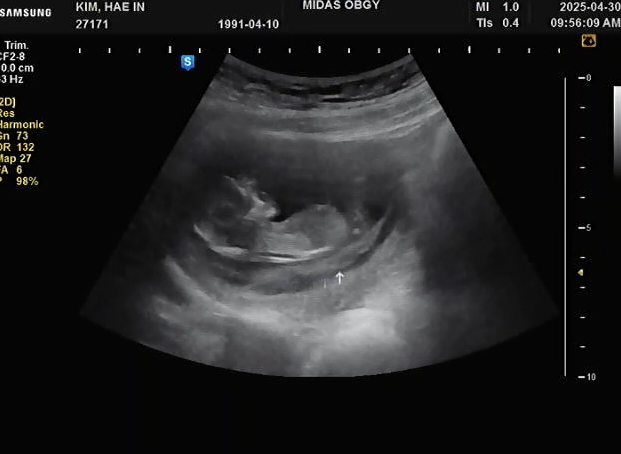

임신11주차 | 갑작스러운 하혈 / 피고임 / 유산방지주사 / 질정제

임신11주차 (25.04.30) 5월 황금연휴를 앞두고 남편 회사가 바빠져서 컨디션도 좋은거같아 잠깐 몇시간 도...